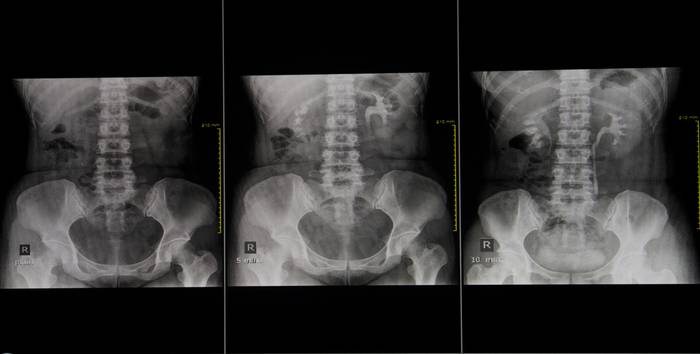

До введения контрастного препарата выполняется обзорная урография – рентгеновский снимок почек и мочевыводящих путей.

Съемка начинается на первых минутах после того, как контраст поступил в кровь, и продолжается от 45 до 60 минут. За это время производится несколько снимков через равные промежутки времени, например, 5-7 минут, затем 12-15, 20-25 и т. д.

При медленном выведении контраста возможно выполнение отсроченной съемки (на 45, 60 минуте). Сколько необходимо сделать снимков, определяет врач-рентгенолог, учитывая особенности заболевания.